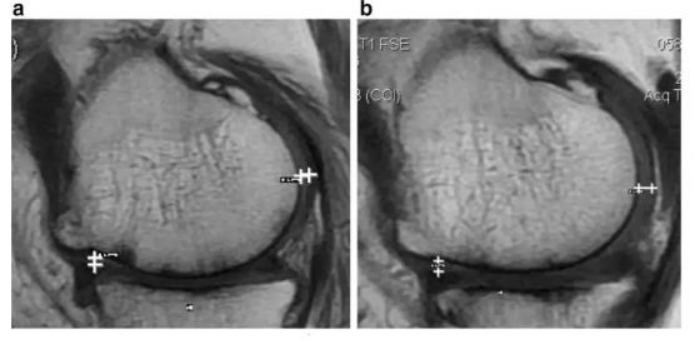

如上图所示,,,,左图为治疗前,,右图为治疗后,,,,白色“+”处示意软骨增厚。。